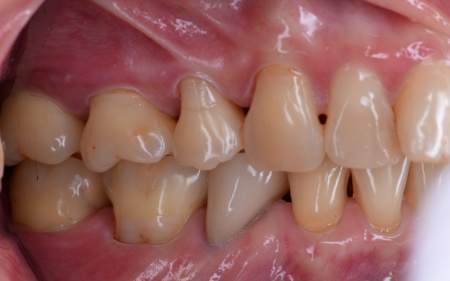

患者様は、歯並びと噛み合わせの根本的な改善を希望されています。

そのため、ワイヤー矯正である程度歯の移動を行ったのち、アライナー矯正(マウスピース矯正)で仕上げを行う矯正治療を提案し、同意いただきました。

2種類の矯正を組み合わせることで、歯をしっかり移動させながら、治療期間の短縮が望めます。

まずはワイヤー矯正を行い、ある程度まで歯並びを整えます。

その後アライナー矯正に移行し、正しい歯並びになるよう調整を行いました。

最後に、噛み合わせや前歯の隙間が改善されたことを確認して、治療を終了しています。